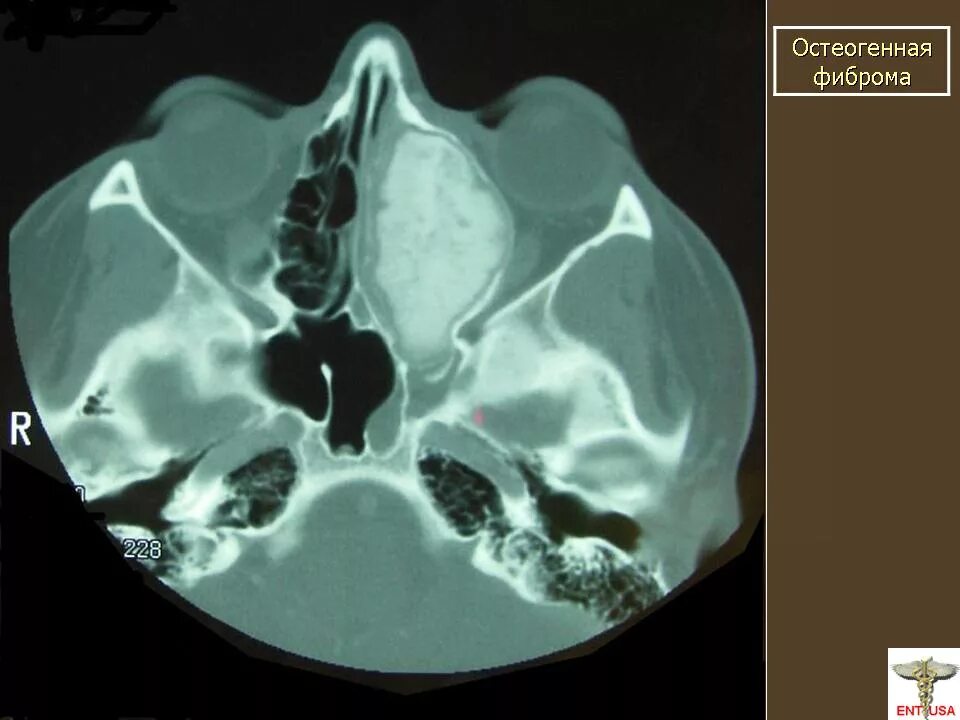

Фиброма кт